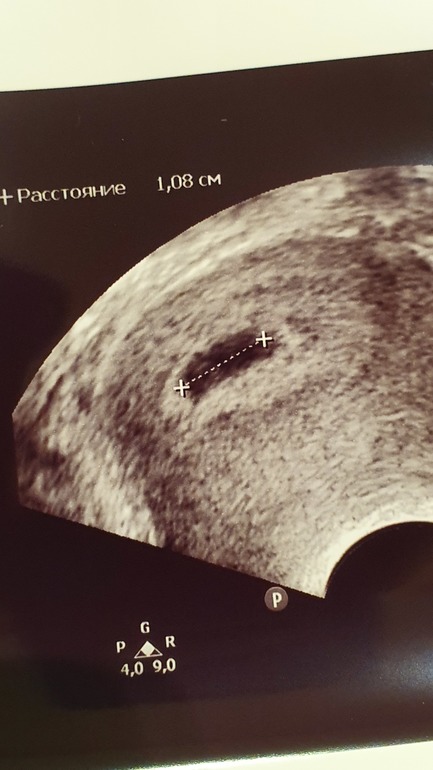

По назначению Г и из-за тянущих болей в пояснице пришла на вот таком сроке на УЗИ, делали не на самом лучшем аппарате

Итог: ПЯ вытянутое 12*4 мм, ЖМ 2,5мм (я его, честно говоря, не увидела), эмбриона не видно

Переживаний масса: вытянутое ПЯ (делали трансвагинально на полный мочевой, так уж вышло. Г предположила, что форма из за мочевого, я переживаю, что из-за тонуса)